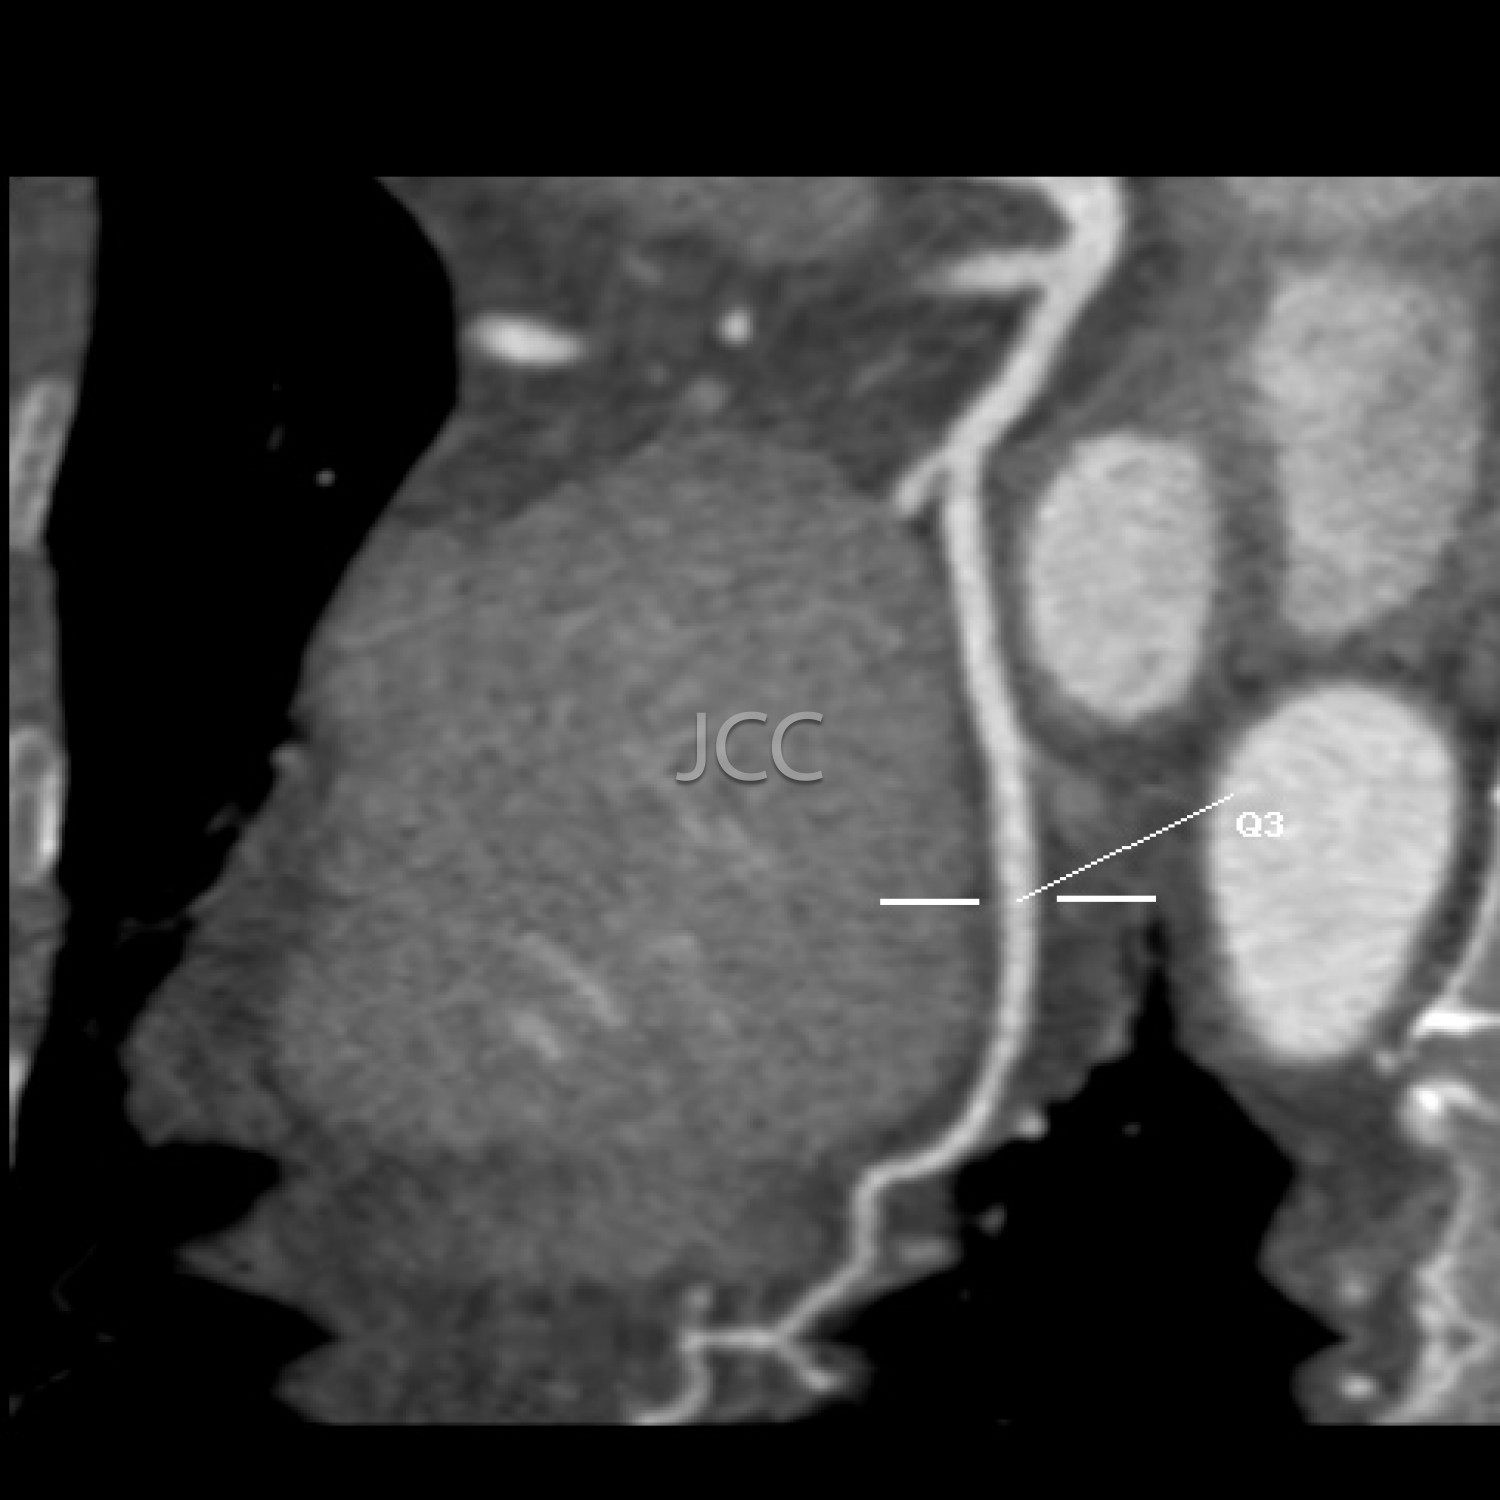

Tomografia Axial Computorizada - ANGIO TAC CORONÁRIAS

A Tomografia Axial Computorizada (TAC) - Dupla Energia - 256 cortes é uma técnica de diagnóstico que permite a avaliação de várias partes do corpo humano, incluindo pulmões, fígado, pâncreas, rins, coração, estruturas vasculares e estruturas ósseas.